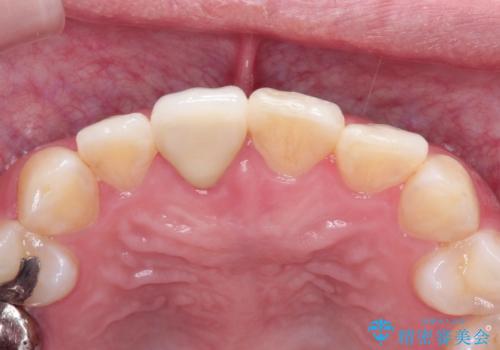

インビザラインにて矯正治療後の前歯のセラミッククラウン治療

インビザラインによる矯正治療で前歯の歯並びを改善し、セラミッククラウン装着により歯の形態の回復をする計画としました。

矯正とセラミックを併用することで、より完成度の高い状態に仕上げることができました。